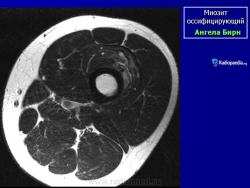

Рентгенологические признаки однотипны для всех форм оссифицирующего миозита; плотный рисунок периферической и менее плотный центральной части повреждения.

Рентгенологические признаки однотипны для всех форм оссифицирующего миозита; плотный рисунок периферической и менее плотный центральной части повреждения.